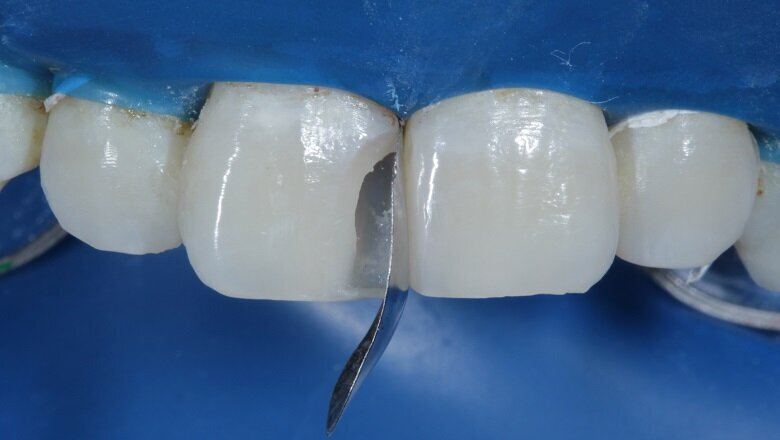

To begin with, the shade (hue) was evaluated using the button technique before isolation. Small balls of different shades of composite (dentin, body and enamel) were placed on the tooth and cured (Fig 4). Value is another important factor which needs to be considered while shade matching.

Fig 4: Shade Evaluation : Button technique (Hue)